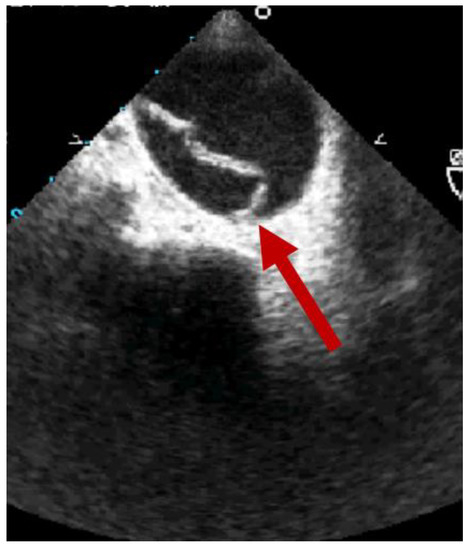

2. Clinical Features of BTAI

3. Diagnosis